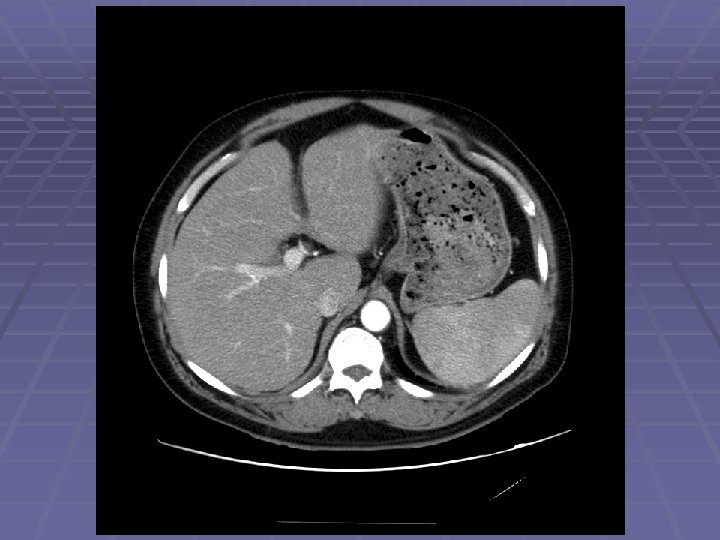

EUS Evaluation of Left Lobe of Liver